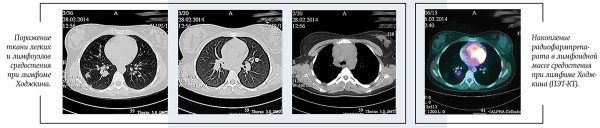

В настоящее время стандартом обследования при ЛХ является позитронно-эмиссионная томография с 18F-флюородезокси-глюкозой, совмещенная с КТ (ПЭТ-КТ).

ПЭТ-КТ позволяет точнее определить вовлеченные в опухолевый процесс лимфатические узлы и области организма, определить стадию и объем лечения. В нашей стране данный метод стал доступен для всех пациентов с ЛХ с 2017 года.

ПЭТ-КТ: в переднем средостении верхнего этажа срединно с акцентом вправо опухолевая масса; 36ґ73ґ60 мм. Изолированно лежащие увеличенные лимфоузлы: паратрахеальные и бифуркационные, до 15 мм; парастернально справа, до 18 мм. По данным ПЭТ: накопление РФП помимо вышеописанных узлов — в правом корне (бронхопульмональные л/узлы), в л/узлах — прекардиально справа, в кардиодиафрагмальной области слева, параэзофагеально (на КТ узел, 14 мм).

Очагов патологической плотности в легочной паренхиме не выявлено. Легочной рисунок не изменен. Долевые и сегментарные бронхи проходимы. Корни легких не расширены, структурны. Подмышечные л/узлы не увеличены. Плевральные полости свободны. Мягкие и костные ткани грудной клетки без структурных изменений. Отмечается увеличение забрюшинных л/узлов, до 23 мм; общих подвздошных до 15 мм. На ПЭТ патологическое накопление РФП помимо вышеописанных узлов — в воротах печени, в наружных подвздошных л/узлах, в селезенке.

Патологических объемных образований в брюшной полости и забрюшинном пространстве не выявлено. Печень не увеличена, однородной структуры. Поджелудочная железа гомогенна, обычных размеров и положения. Почки без видимых изменений.

В левой подвздошной кости определяется очаг гиперденсивной плотности с мелкобугристыми контурами, размером 10,5ґ6,6 мм. На ПЭТ также отмечается повышенное накопление РФП в телах позвонков С6, Тн4, L5, S1; ребрах; костях таза.

Заключение: лимфопролиферативное заболевание с поражением лимфоузлов по обе стороны диафрагмы, селезенки, костей.

Получен полный метаболический ответ по данным ПЭТ-КТ после этапа ПХТ. С целью консолидации ремиссии проведена лучевая терапия на зоны инициального поражения в СОД=20 Гр.